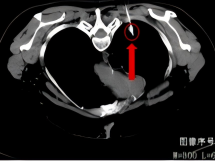

2011年,一名70岁患者因出现咳嗽、咳痰带血等症状就诊于我院呼吸门诊,在完善CT等相关检查后,患者被诊断为右上腺癌(多原发),在充分的与患者及家属进行沟通后,明确表示不接受外科手术,科室为患者制定并实施了CT引导下经皮肺穿刺射频消融+碘125粒子植入放疗+化疗的治疗方案。

术 前

术 后

患者分别在治疗4月和1年后复查胸部CT显示病灶稳定,病情得到进一步控制。